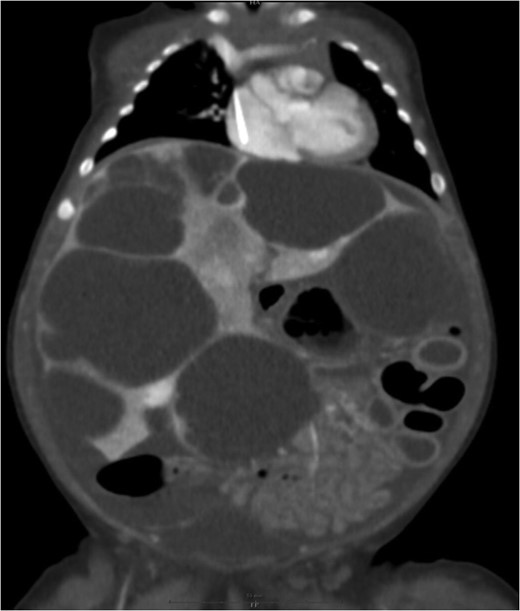

Abdominal ultrasound showed enlarged liver with multi nodular hypo-hyperechogenic hepatic lesions with complete distortion of hepatic vasculature. Computed tomography (CT) scan with contrast injection showed co-existing multifocal hepatic solid and macro-cystic lesions with no hepatic calcifications (Fig. 1).

Large cystic lesions with internal septation associated with heterogeneous small solid lesions with arterial enhancement.